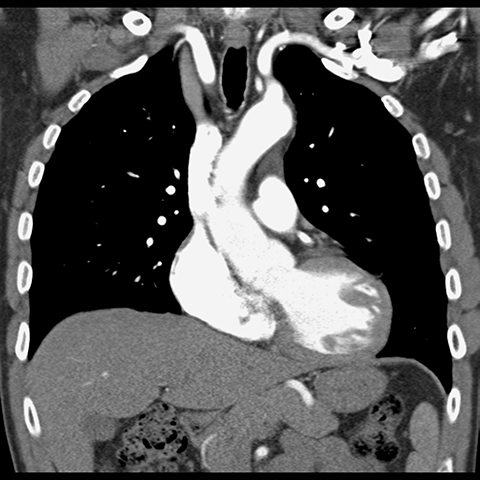

Coronal CT Angiography (Mediastinal Window) [1 of 2]